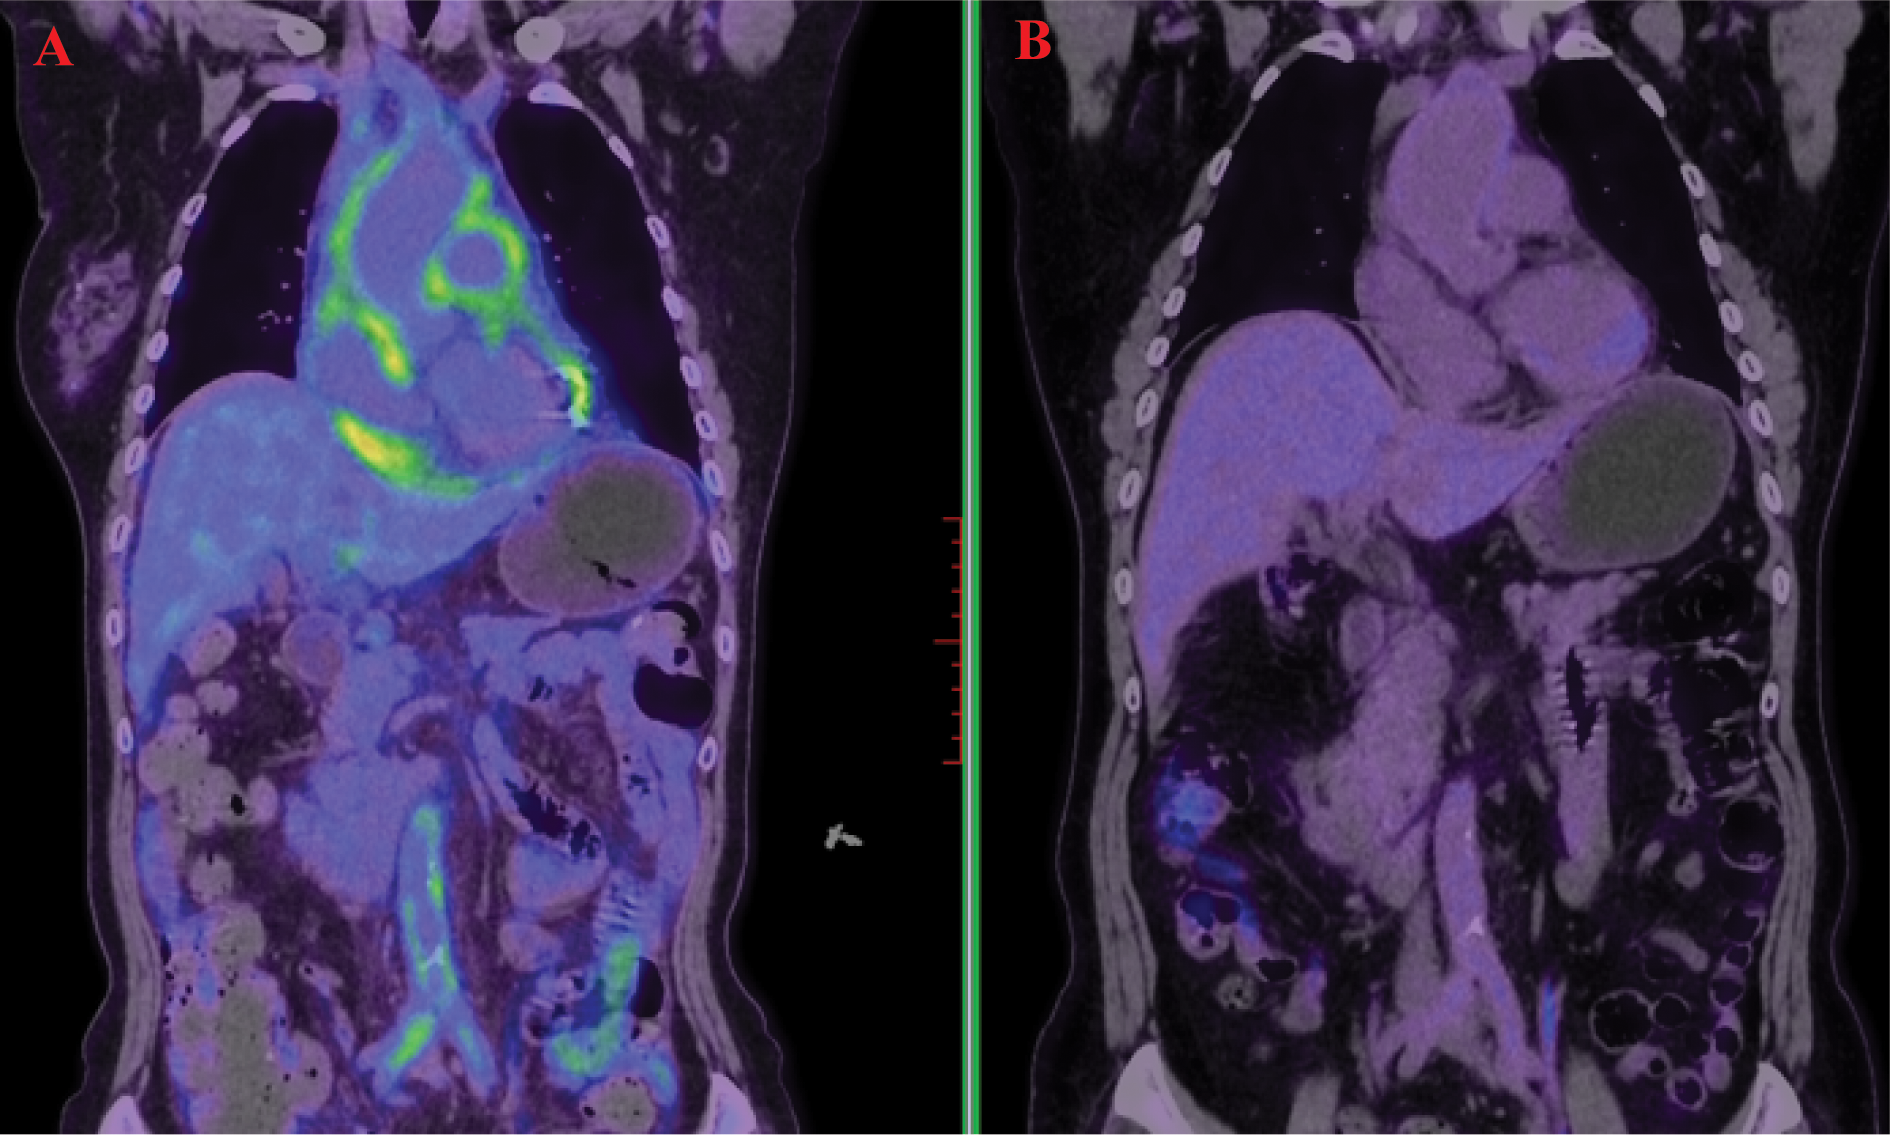

A 66-year-old female patient was admitted on November 3, 2022, with chief complaints of chest tightness and dyspnea. Cardiac magnetic resonance imaging (MRI) revealed extensive thickening of the pericardium and irregularly shaped tissue that had infiltrated the wall of the right atrium, also impacting the interatrial septum. The 18F-Fluorodeoxyglucose positron emission tomography/computed tomography (18F-FDG PET-CT) exhibited significant uptake in the right atrial wall, interatrial septum, pericardium, pulmonary artery, aorta, and vena cava (Figure 1A). The patient subsequently underwent pericardial window surgery and biopsy, during which pericardial adhesions and nodular changes in the epicardial fat were observed. Histopathological examination showed abundant foamy histiocytes and multinucleated giant cells within the pericardium and surrounding adipose tissue. Immunohistochemistry revealed CD163(+) and CD68(+) expression in foamy cells, while Langerin, CD1a, and BRAF were negative (Figure 2). These findings led to a diagnosis of Erdheim-Chester disease (ECD).

Figure 1

18F-Fluorodeoxyglucose positron emission tomography/computed tomography (FDG-PET/CT) demonstrated high uptake in the pericardium, aorta, abdominal aorta, and bilateral iliac artery walls (A). A follow-up scan after treatment showed marked metabolic reduction in these previously uptake regions (B).

The patient received combination therapy with subcutaneous interferon-α (3 million IU three times weekly) and cladribine (4 cycles of 7-day infusions at 4-week intervals). A significant reduction in metabolic lesions was observed following combination therapy (Figure 1B). Interferon-α monotherapy (3 million IU subcutaneously weekly) was continued as maintenance therapy for 12 months, with disease surveillance via MRI every 6 months. No grade ≥2 adverse events occurred during this phase. Follow-up involved cardiac ultrasonography and lab tests including CBC, liver/renal function, CRP, ESR, IL-6, and BNP. To date, the patient remains in stable condition with no disease progression.